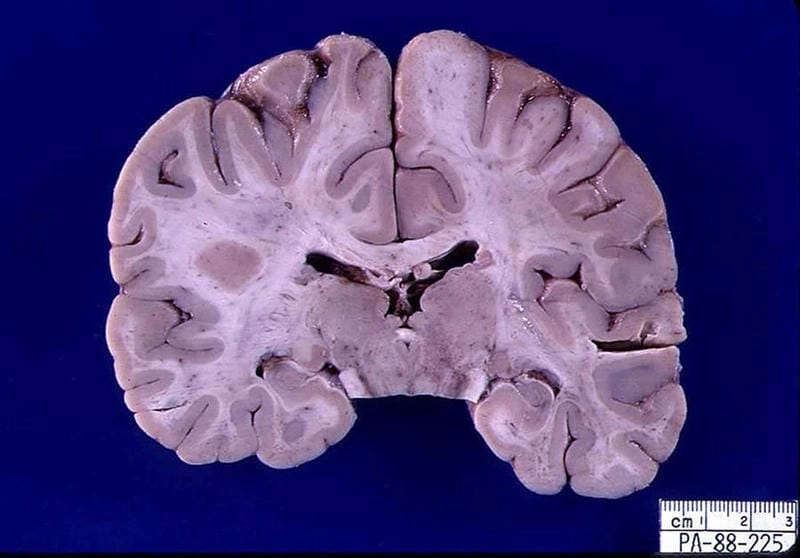

Image description of La Crosse Encephalitis

La Crosse Encephalitis is a rare viral disease spread by mosquitoes. It primarily affects children and can lead to fever, headache, seizures, and neurological complications in severe cases.